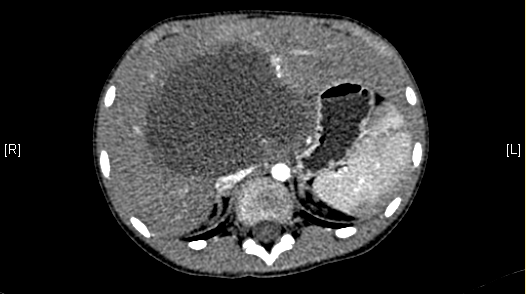

术前CT检查:

动脉期

腹部超声示:肝内包块。腹部CT:肝脏占位,血管瘤?上腹部增强CT:肝左内叶-右前叶交界区、尾叶囊实性团块影,考虑肿瘤(胆管囊腺瘤?间叶性错构瘤?)